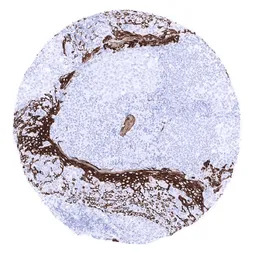

IHC-P analysis of human tonsil tissue section using GTX04411 Cytokeratin 15 antibody [MSVA-615M] HistoMAX.

In tonsil krypts a strong KRT15 immunostaining is found in all cell layers of squamous epithelium.